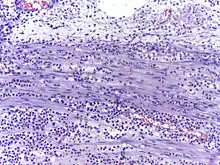

In autopsy, the presence of neutrophils in the heart or brain is one of the first signs of infarction, and is useful in the timing and diagnosis of myocardial infarction and stroke.

Neutrophils are seen in a myocardial infarction at approximately 12–24 hours,[66] as seen in this micrograph.